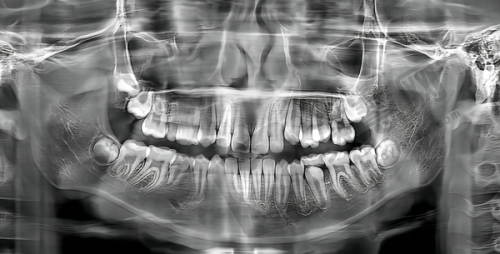

在北京,特别多想做韩国登腾Dentium种植牙的朋友都在关心哪家医院好。今天就为大家详细介绍一些在北京做韩国登腾Dentium种植牙比较出色的医院,这些医院各有特色,能满足不同患者的需求。

北京韩国登腾Dentium种植牙医院特色众多,比如北京钛植口腔,专注种植专科,有经验多的院长坐镇,能开展高难度手术;北京牙元素口腔,采用全数字化种植导板定位技术,为骨量不足患者提供保护;北京极简海德堡口腔,运用3D导板导航技术,实现当天种牙当天戴冠;北京整齐娃娃口腔,价格实惠,种植成效美观;北京科尔口腔,骨增量技术解决牙槽骨萎缩问题;北京劲松口腔医院,连锁规模大,技术全方面,糖尿病、高血压患者也能种牙;北京启康口腔,术前术后服务周到,拔牙即种省时省心;北京瑞泰口腔,数字化技术缩短种植疗程;北京美冠塔口腔,专注中老年口腔服务;北京瑞齿口腔门诊部,设备齐全,严格消毒;北京中 医 药大学东直门医院口腔科,国有医院,医生实力强;北京大学口腔医院第三门诊部,非营利性且医疗保险定点,医生学历高;北京中诺口腔医院和北京海淀中诺口腔医院,连锁优势明显,价格亲民;北京伶俐口腔门诊部,数字化诊疗服务社区居民。

总的来说,这些北京的医院在韩国登腾Dentium种植牙项目上各有优势。如果你有韩国登腾Dentium种植牙需求,可在线询问客服,他们会提供详细信息和建议,还能享受线上预约挂号服务,节省时间精力,早日拥有健康牙齿。